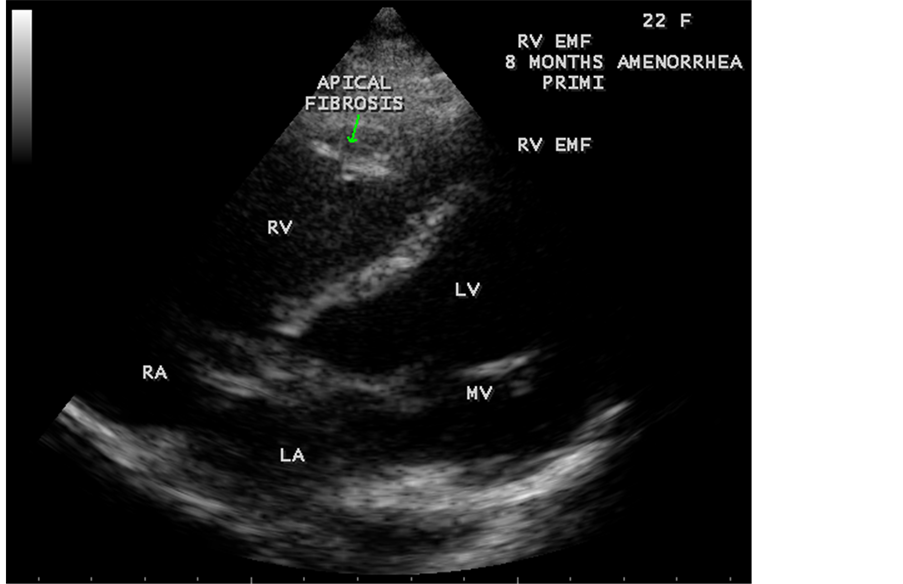

Figure 67. RV EMF in a 22-year-old female antenatally (8 months amenorrhea-primigravida).

RV EMF was detected antenatally in a 22-year-old woman with 8 months amenorrhea as in Figure 67. Endomyocardial fibrosis with left ventricular endocardial calcification and subvalvular fibrosis was detected in a new born with complete AV (atrioventricular) septal defect as shown in Figure 68 to Figure 72. EMF associated with fibrosis of papillary muscle and aneurysmal left ventricle is shown in Figure 74 and Figure 75 in a 56-year-old female. RV EMF associated with right sided pleural effusion, massive ascites and smoke (spontaneous echo contrast) in both ventricles are shown in Figure 76 to Figure 82 in a 42-year-old male. Classical case of RV EMF was shown in Figure 83 and Figure 84 in a 55-year-old male.